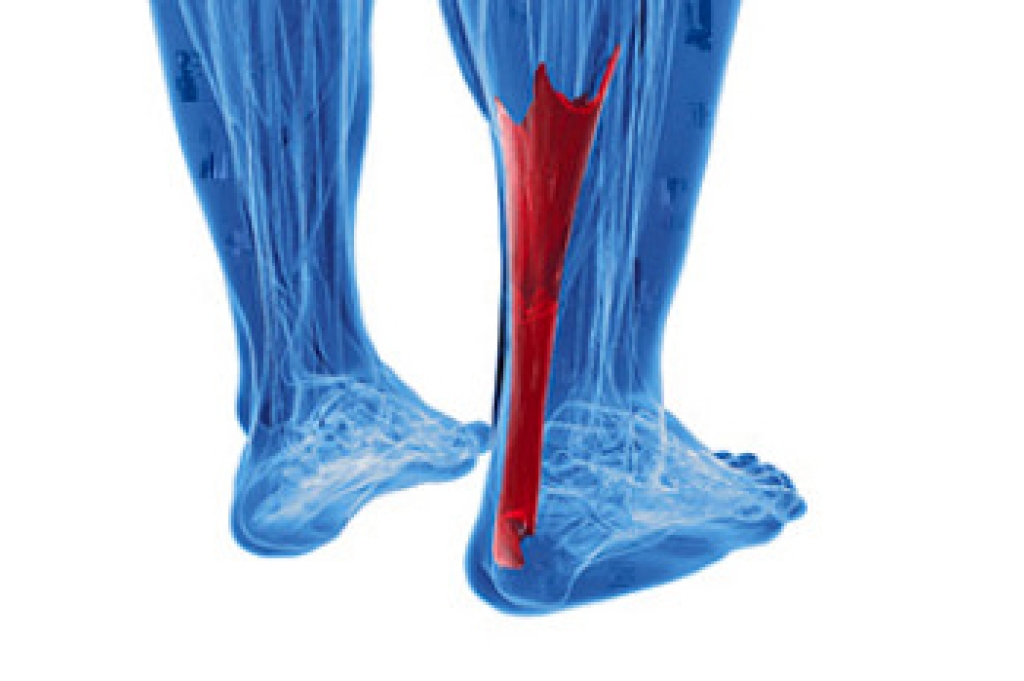

Foot and ankle injuries are a common occurrence when it comes to athletes of any sport. While many athletes dismiss the initial aches and pains, the truth is that ignoring potential foot and ankle injuries can lead to serious problems. As athletes continue to place pressure and strain the area further, a mild injury can turn into something as serious as a rupture and may lead to a permanent disability. There are many factors that contribute to sports related foot and ankle injuries, which include failure to warm up properly, not providing support or wearing bad footwear. Common injuries and conditions athletes face, including:

- Plantar Fasciitis

- Achilles Tendinitis

- Achilles Tendon Rupture

- Ankle Sprains

Sports related injuries are commonly treated using the RICE method. This includes rest, applying ice to the injured area, compression and elevating the ankle. More serious sprains and injuries may require surgery, which could include arthroscopic and reconstructive surgery. Rehabilitation and therapy may also be required in order to get any recovering athlete to become fully functional again. Any unusual aches and pains an athlete sustains must be evaluated by a licensed, reputable medical professional.